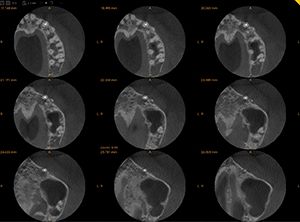

Photos 4 – 5 – 6 : En imagerie conventionnelle, on constate une lésion d’origine endodontique sur la 26, mais la 2D ne nous informe pas sur la situation de cette lésion et ses rapports avec le sinus maxillaire. Sur la coupe axiale, on voit parfaitement l’étendue de la lésion. Sur les coupes coronales obliques, on constate la parfaite étendue de cette LOE et on vérifie en même temps les dents adjacentes prises dans la même acquisition.